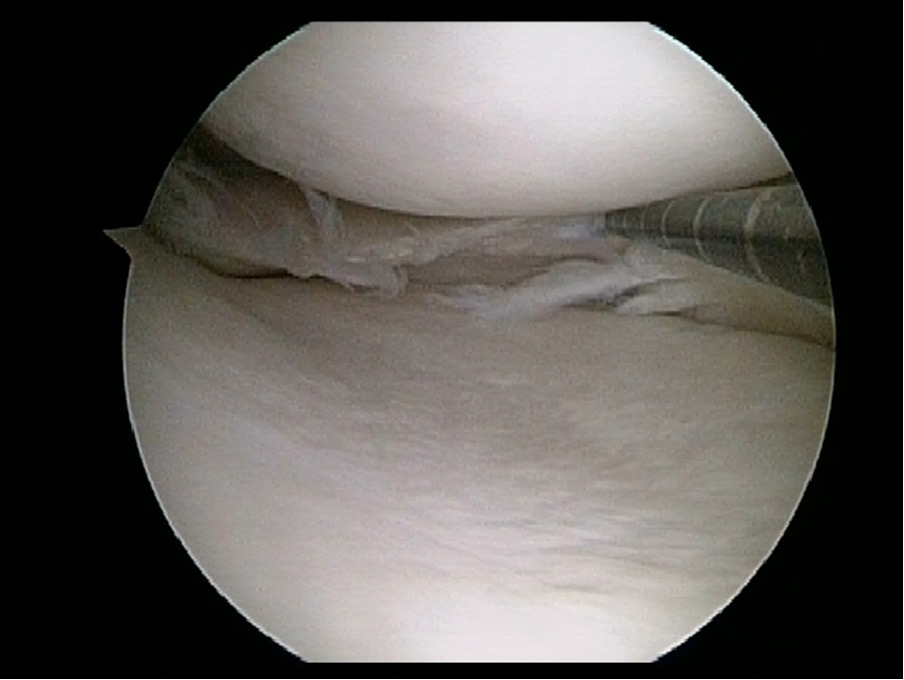

Posterior Root Medial Meniscus Tear With Medial Opening Wedge High Tibial Osteotomy A Step By Step Systematic Arthroscopic Repair Technique Arthroscopy Techniques

If you have a partial or total meniscectomy you can. This cartilage is called the meniscus. Arthroscopy ahr-THROS-skuh-pee is a procedure for diagnosing and treating joint problems.

Outside In Repair Of Longitudinal Tear Of Medial Meniscus Suture Shuttle Technique Sciencedirect

Meniscus Tears Diagnosis Repair Techniques And Clinical Outcomes Musculoskeletal Key